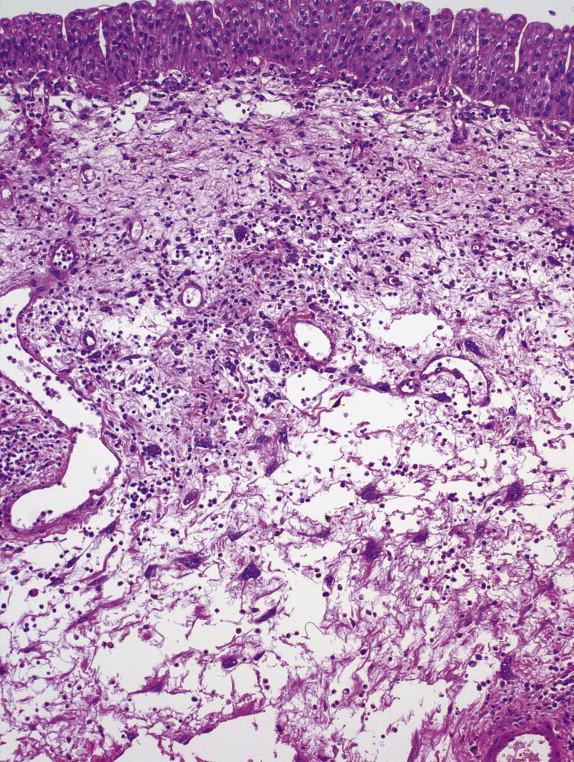

There are no characteristic histologic features for interstitial cystitis. The nonulcerative disease has a relatively unaltered mucosa with a sparse inflammatory response. The main feature is multiple small mucosal ruptures and suburothelial hemorrhages ( Fig. 3-20 , A ). The bladder mucosa may be completely normal in some cases and denuded in other cases. In patients with Hunner ulcer, the ulcer varies in thickness but usually involves the upper half of the lamina propria. It is often covered by debris, fibrin, inflammatory cells, and erythrocytes. The ulcer base is composed of granulation tissue. The rest of the lamina propria is moderately or markedly inflamed with lymphoid

aggregates. Perineural inflammation ( Fig. 3-20 , B ), or chronic perineuritis, is seen in 70% of patients. In long-standing diseases, fibrosis and inflammation may be seen in the muscularis propria ( Fig. 3-20 , C ), a finding that correlates with the reduced bladder capacity seen in advanced disease. The perivesical fat usually lacks significant inflammation.

FIGURE 3-20, Interstitial cystitis: microscopic features. A, The bladder mucosa has small mucosal rupture and subepithelial hemorrhage. B, Perineuritis is present. C, In long-standing cases, trichrome stain reveals extensive fibrosis of lamina propria and muscularis propria.